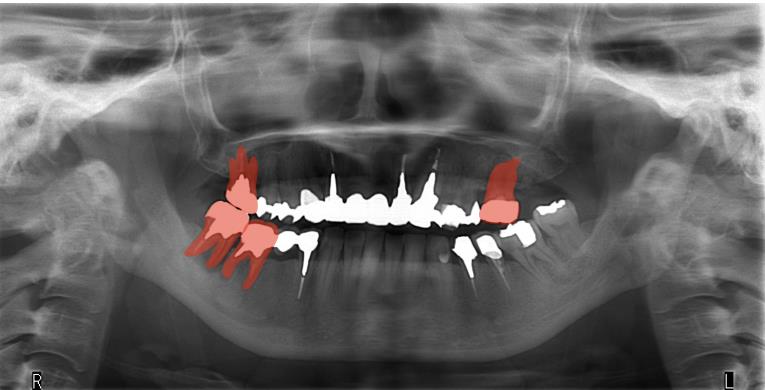

患者は40代女性で、上の歯が前に出ていることで噛みにくく、見た目も良くしたいとの理由で来院されました。奥歯の数は少なく、特に左上は大臼歯がありませんでした。上下の歯の真ん中のラインは大きくずれており、昔に入れた前歯の被せ物は変色し、審美障害を呈してました。(図1、2)